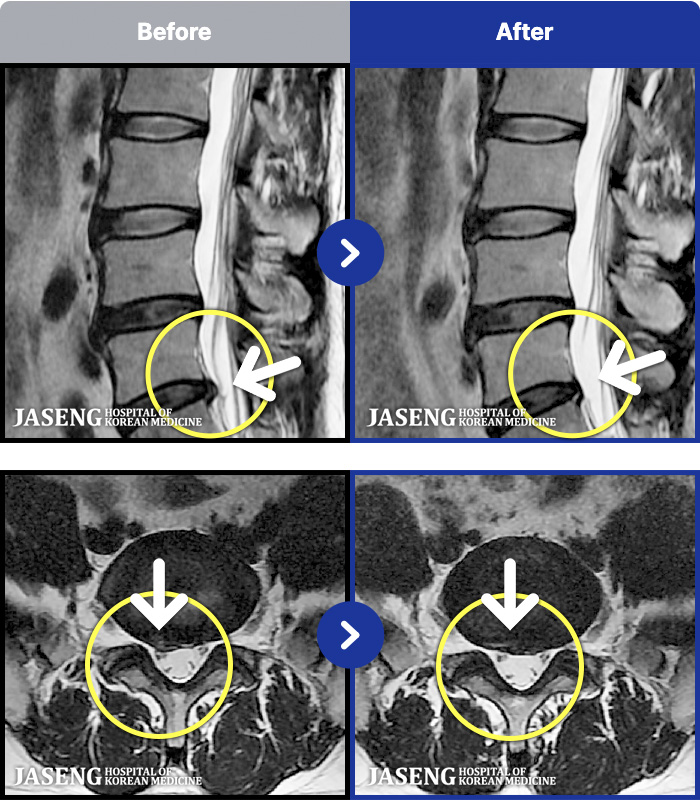

- MRI ġ

MRI ġ

1,237 MRI ũ ʸ Ȯϼ.